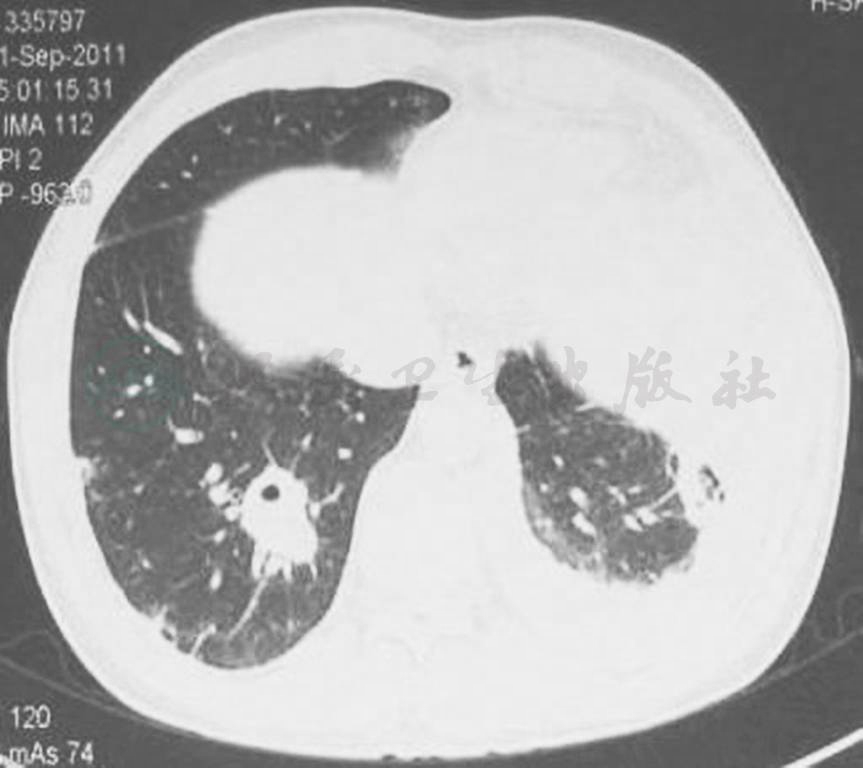

图2 胸部CT表现(2011-08-18)

胸部CT显示双肺阴影较前增多、加重,并出现双侧胸腔积液,左侧明显